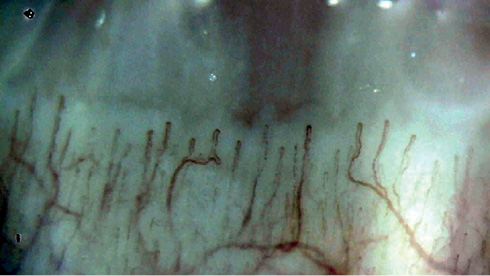

Рис. 1 Изменение капиллярного русла у пациента с системной склеродермией.

Примечание: редукция капиллярного русла (3-4 капилляра/мм2), расширение и извитость капиллярной петли, значительное снижение скорости микроциркуляторного кровотока. Микрогеморрагии отсутствуют (увеличение ×250; собственные данные).